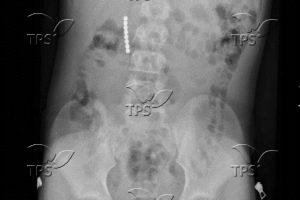

Magnetic balls found in the body of an Israeli child who was hospitalized after swallowing them. Photo by Bnei Zion Medical Center/TPS-IL